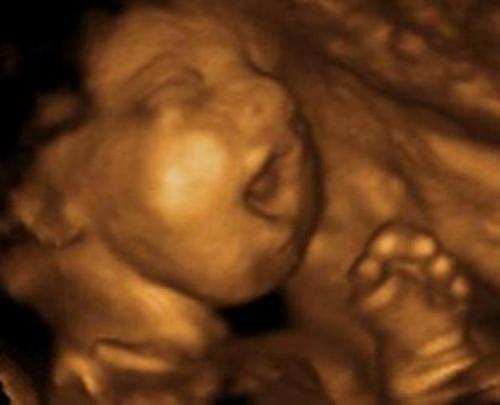

Британска докторка направила восхитувачка јасна 4Д слика на бебе, кое се проѕева во матката. Животот на бебињата во стомакот на мајката се покажува дека е многу покомплексен, од она што се веруваше пред напредокот на ултразвучната технологија. Се чини како неродените бебиња да имаат свој таен универзум, во чии тајни науката тек треба да проникне. Нивните уникатни личности се развиваат толку мистериозно и забрзано уште од самиот момент на зачнувањето.

Во минатото научиниците не можеа точно да утврдат дали неродените бебиња само ја отвораат устата или вистински се проѕеваат. Со сега Др. Nadja Reissland, од Универзитетот во Дурам, со помош на подетална ултразвучна техника успела да добие слики од лицето на бебињата, од кои јасно може да се направи разлика помеѓу отворање на устата и проѕевање. Таа вели: